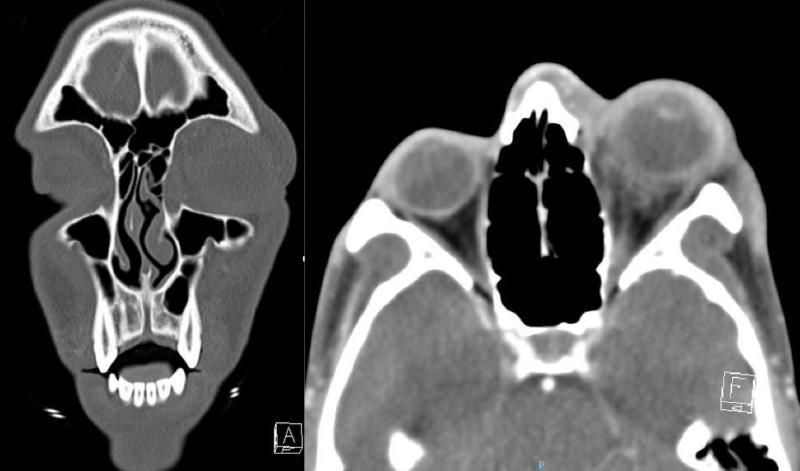

Computed Tomography of the Orbit at presentation Left (Coronal), Right (Axial) revealing fat stranding without any visible scleral abscess at presentation.

| current | 14:31, April 27, 2023 | 1,612 × 950 (2.03 MB) | Fabliha.Anbar (talk | contribs) | Computed Tomography of the Orbit at presentation Left (Coronal), Right (Axial) revealing fat stranding without any visible scleral abscess at presentation. |